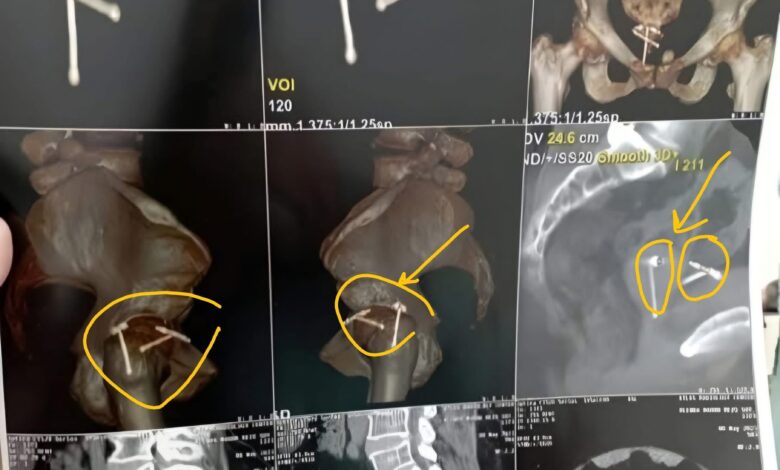

استمرت المريضة في معاناتها لفترة طويلة حتى خضعت لفحوصات دقيقة في مركز طبي متخصص، حيث أظهرت الأشعة المقطعية أن اللولب الأول كان مخترقًا جدار المثانة ومغطى ببعض الحصوات، بينما كان اللولب الثاني موجودًا داخل الرحم، مع حصوات في قناة مجرى البول.

تم إعداد خطة جراحية دقيقة بالتعاون بين استشاريي المسالك البولية وجراحة النساء، تضمنت إزالة حصوات المثانة بالمنظار، ثم فصل اللولب الأول واستئصاله، وإغلاق جدار الرحم والمثانة، وإجراء تدخل لرفع اللولب الثاني عبر فتحة أمامية للرحم. بعد الجراحة المعقدة، خرجت المريضة من المستشفى بصحة جيدة، مؤكدة نجاح الفريق الطبي بقيادة د. أمير فايق، استشاري جراحة ومناظير الكلى والمسالك البولية، وفريق العمل المساعد.